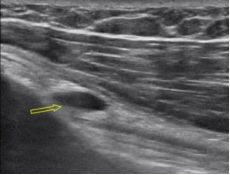

高频超声探头体表外深入肌肉组织、骨骼细胞图